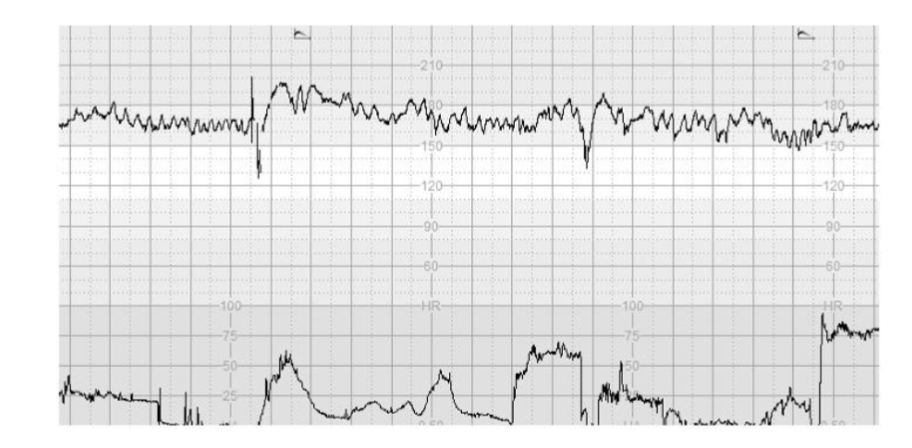

Figure 1 illustrates >10% increase in the baseline FHR without repetitive decelerations, absence of cycling and presence of the “Poole Shark Teeth Pattern” six hours after spontaneous rupture of membranes.

Figure 1. CTG trace illustrates >10% increase in the baseline FHR without repetitive decelerations, absence of cycling and presence of the “Poole Shark Teeth Pattern”, which are the features of SOFI, following SROM.